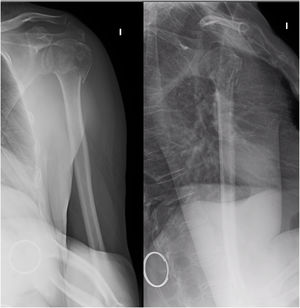

Material and methodThis is a prospective, observational study of a series of consecutive cases: patients who presented to the Emergency Department of our hospital and who were diagnosed with a fracture of the proximal end of the humerus between 1 March and 30 June 2017. The inclusion criteria for the study were: subjects aged 18 years or older, from the reference population of our healthcare district, who exhibited a fracture of the proximal humerus and who voluntarily agreed to participate in the study and to undergo a neurophysiological evaluation (an EMG and electroneurogram) as diagnostic tests in addition to conventional treatment of the fracture; i.e., conservative therapy or surgical intervention. Enrolment in the study did not affect the treatment decision (conservative or surgical); they were treated with the standard treatment that we provide during clinical care. The neurophysiological study was scheduled approximately 20 days after the fracture, as this is regarded as the optimal time for early detection of injury to this nerve with this test. This was done in those cases that received conservative treatment with immobilisation in a sling. The neurophysiological study performed consisted of both an EMG and an electroneurogram. Comparison was made with the contralateral arm as a control. In addition, in cases where axillary nerve injury was noted, the EMG and electroneurogram were repeated at one month as a control. The neurophysiologist who participated in the study is an experienced professional. Exclusion criteria comprised: diseases that could affect the baseline EMG recording (diabetes mellitus [DM], polyneuropathy, myopathy, motor neuron disease, hypothyroidism, or hyperthyroidism), anticoagulant treatments, such as acenocoumarol or warfarin, or advanced dementia as well as other diseases that may hinder the patient's cooperation during the neurophysiological study. Patients with pathological fractures were not included, nor were those who were seen at the Emergency Department of our Hospital, but were followed up at a different centre. Finally, no patients who had previously undergone shoulder surgery were included (Fig. 1).

During the initial assessment, the fractures were classified according to the AO classification (Arbeitsgemeinshaft für Osteosynsthesefragen, Association of the Working Group for the Study of Internal Fracture Fixation) as type AO11A, unifocal extra-articular; AO11B, bifocal extra-articular, and AO11C, articular (Fig. 2), and then were then subclassified into the groups of this classification (Table 1).

AO classification of proximal humerus fractures.